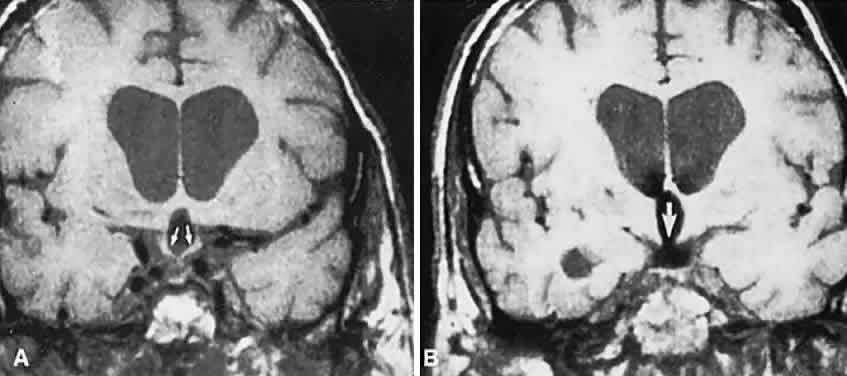

Clinical signs and symptoms include the following: acute onset of severe headache, often sickening frontal or retro-bulbar cephalgia, or other less disabling change in headache pattern; acute or rapidly progressing unilateral or bilateral (usually asymmetric) ophthalmoplegia due to rapid expansion into cavernous sinuses (see also Volume 2, Chapter 12); epistaxis or CSF rhinorrhea when the mass ruptures or erodes into the sphenoid sinus; complications of blood or necrosis debris in the CSF, with “pseudomeningitis”; rapid neurologic deterioration and obtundation, although patients need not be stuporous; and, greater or lesser degrees of hypopituitarism.62,63 Selective expansion laterally into the cavernous sinus may produce ophthalmoplegia without visual loss; selective expansion superiorly may produce visual loss without ophthalmoplegia. Almost without exception, enlargement of the sella is found even on plain skull film views; both CT and MRI detect fresh hemorrhage (Fig. 3), but MRI may fail to demonstrate acute hemorrhage unless specific sequences are employed (hemorrhage may be isointense on T1-weighted images and hypointense on T2-weighted images; in the subacute phase, extracellular methemoglobin should appear bright on both T1 and T2 sequences). Corticosteroid replacement and other supportive measures may be critical, and, in most instances, decompression through the sphenoid sinus is advisable, sooner rather than later. Bromocriptine has been suggested as a temporizing measure when signs and symptoms are modest and not progressing,64 and there are advocates65 for conservative management consisting of intravenous dexamethasone, so long as visual deficits are minimal or rapidly improve; otherwise decompressive surgery is required. Given the regularity with which pituitary apoplexy is often a delayed diagnosis, being confused with ruptured aneurysm or meningitis, for example, and that transsphenoidal surgery is a relatively simple undertaking, further procrastination in decompression of the compromised visual pathways is to be avoided.

Fig. 3. Neuroimaging of pituitary adenomas. A. Axial computed tomography (CT) section shows a round tumor mass filling the suprasellar cistern; ring enhancement (arrows) indicates subcapsular hemorrhage. B. Contrast-enhanced coronal CT section through a large invasive adenoma. Note encasement of the carotid artery (arrows) and the position of the middle cerebral artery above (arrowheads). C. Axial CT section shows lateral expansion into the cavernous sinuses (white arrows) and a necrotic cyst (black arrow). D. Subfrontal superior extent of the mass. Note the middle cerebral arteries. E. Magnetic resonance imaging of a large lobulated prolactinoma, with suprasellar extension. Note the distortion of the third ventricle (open arrows) and extension toward the temporal lobe (long arrow); the tumor has not involved the sphenoidal sinus (s). F. Chiasm (arrowheads) is draped on the superior surface of the tumor (TR, 550 milliseconds; TE, 26 milliseconds). G. Sagittal section shows suprasellar growth with the chiasm above (arrowheads); the sella (arrows) and sphenoidal sinus (s) are normal (TR, 850 milliseconds; TE, 26 milliseconds). H. Hyperintense signal (TR, 2000 milliseconds; TE, 60 milliseconds) indicates the partial cystic character. Sagittal (I) and axial (J) sections with head tilt to the right, in case of a large cystic adenoma with an interface level between newer blood (white arrow) and older blood (black arrow) (TR, 800 milliseconds; TE, 30 milliseconds). K. Signal difference is intensified (TR, 2100 milliseconds; TE, 80 milliseconds). L. Hemorrhage (bright signal, arrow) in a pituitary adenoma with headache and bitemporal field depressions. M. Without interventions, 2-month follow-up showed spontaneous involution, with normal pituitary gland (arrow), stalk, and chiasm.